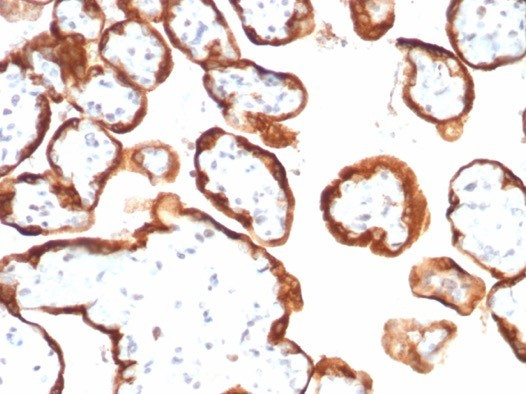

HCG-beta (Pregnancy and Choriocarcinoma Marker) Antibody in Immunohistochemistry (Paraffin) (IHC (P))

HCG-beta (Pregnancy and Choriocarcinoma Marker) Antibody (1081-MSM8-P0) in IHC (P)

Formalin-fixed, paraffin-embedded human placenta stained with HCG-beta Mouse Monoclonal Antibody (hCGa/7138). HIER: Tris/EDTA, pH9.0, 45 min. 2: HRP-polymer, 30 min. DAB, 5 min. {{ $ctrl.currentElement.advancedVerification.fullName }} 验证信息 View more